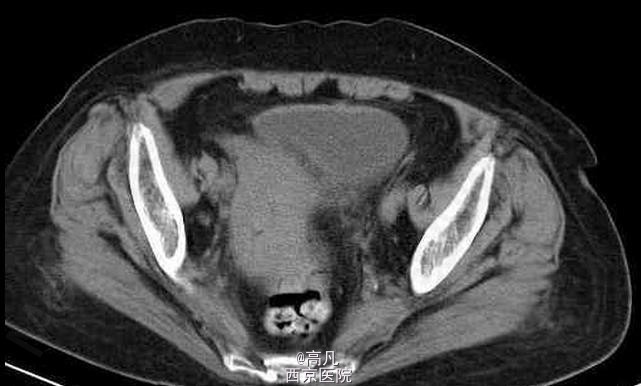

临床一例子宫内膜癌

子宫内膜癌

女,70岁,因近日来阴道不规则出血前来就诊

不规则阴道出血,常为少量至中等量的出血,有稀薄的白色分泌物 辅查CT,MRI,CT表现常可见宫体不均匀增大, MRI示子宫内膜增厚,T2WI上内膜信号不均,部分可见宫内低信号连接带中断

子宫内膜癌 处理:以手术为主,配合化疗及放疗